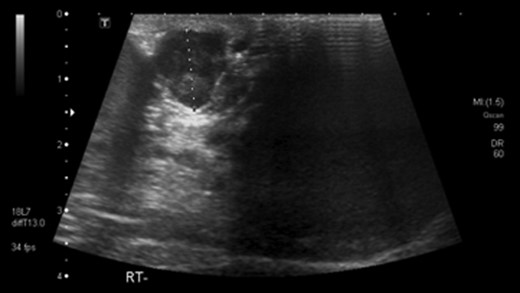

He had undergone ultrasound investigation for the same complaint 3 years prior to his referral which demonstrated a bulky right epididymis with focally increased vascularity, thought to be a benign sperm granuloma (Fig. 1). Repeat USS 3 months later again showed some inflammatory thickening of the right epididymis and no further action was taken.

Ultrasound scan showing paratesticular leoimyosarcoma 3 years prior to referral.